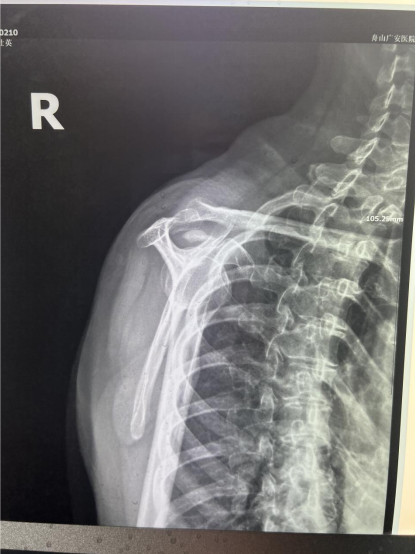

賀大媽慕名來廣安醫(yī)院找羅軍主任就診,面對羅醫(yī)生,賀大媽哭訴:“羅醫(yī)生,我真想剁下自己的這只胳膊。”羅軍主任根據(jù)患者的癥狀拍片,診斷為岡上肌鈣化性肌腱炎,隨后,羅醫(yī)生為李大媽進行了肩關(guān)節(jié)鏡微創(chuàng)手術(shù),竟從她的右肩“擠”出“牙膏”。

是不是只要病人撐得住,讓鈣鹽吸收就沒事了?羅軍主任表示,經(jīng)保守治療無法緩解或病程長的患者,應(yīng)盡早采取手術(shù)治療。而且,部分患者鈣鹽無法完全吸收,拖下去只會使病情惡化,造成肩膀肩袖肌腱的損傷。

羅軍主任表示,很多人會把肩痛都歸因于肩周炎,這是一個很大的誤區(qū)。其實,肩痛人群中只有15%左右是肩周炎,大部分肩膀疼痛由于肩袖損傷、肩峰撞擊征、鈣化性肌腱炎。而大多數(shù)人也因此認為忍一忍就會自愈,常常延誤治療,關(guān)節(jié)鏡微創(chuàng)治療鈣化性肌腱炎,可以快速緩解疼痛,同時可以修復(fù)肩袖損傷,清理肩膀骨刺。